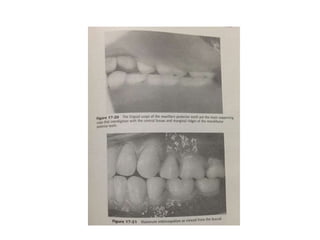

The document discusses arranging artificial teeth in complete dentures, including positioning the maxillary central incisor, using lingualized occlusion for balanced occlusion and stable dentures despite mandibular movement, and employing buccal offset setting of the maxillary teeth following the contour of the ridge so that the lower teeth will follow the upper teeth. It also mentions the power of using masking tape in the denture process.